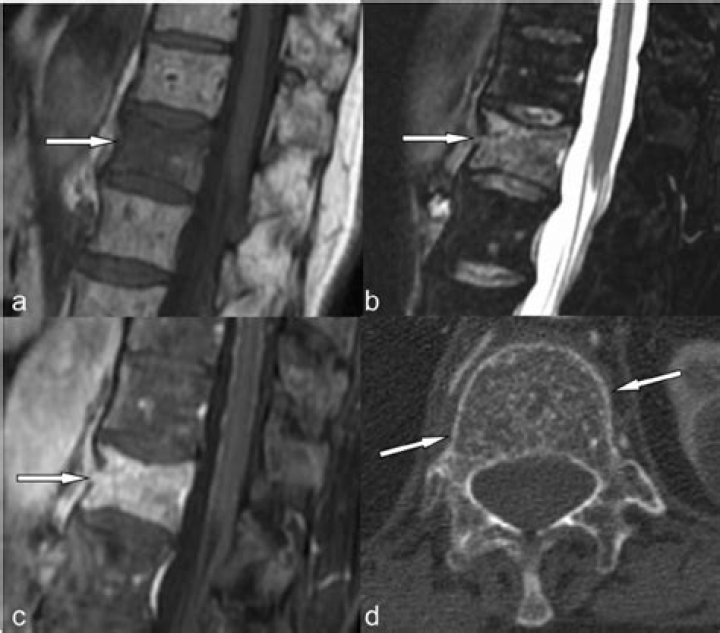

Atypical hemangiomas, which may vary in appearance, include those that are hypointense on T1-weighted images but retain the typical characteristics on T2-weighted and fat-suppressed postcontrast images (2).

Atypical Hemangioma in Spine A spinal hemangioma or a hemangioma in spine is a benign tumor that may develop in the bony segments of the spinal column. The term hemangioma refers to a mass of blood vessels that commonly occur on the subcutaneous tissues.